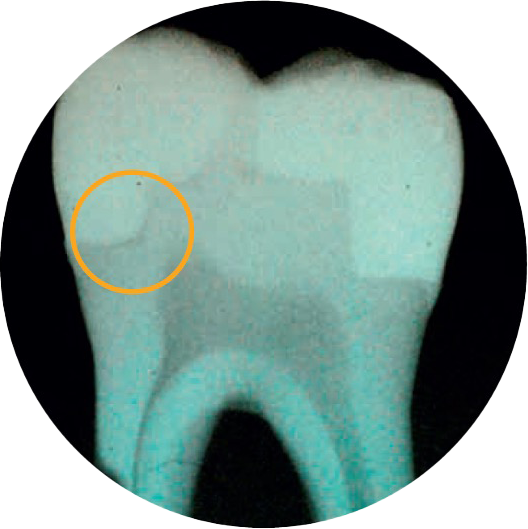

Não tem a certeza em relação à formação de falhas?

O material SDR flow+ é uma inovação única na medicina dentária - um bulk fill fluido que combina propriedades exclusivas autonivelantes e o melhor stress de encolhimento da categoria - que permite a colocação até 4 mm com excelente adaptação da cavidade, permitindo a colocação de restaurações sem falhas.